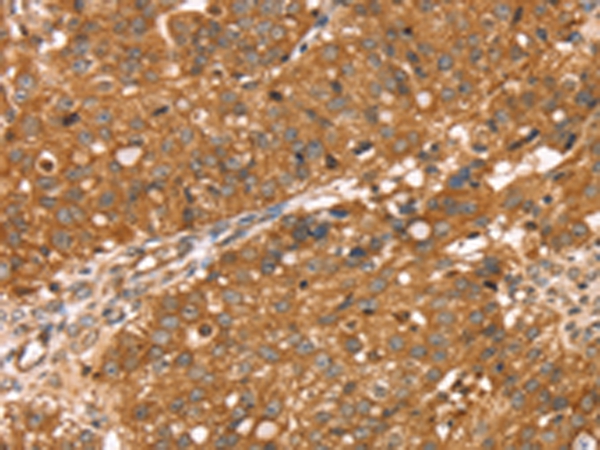

Immunohistochemical analysis of paraffin-embedded Human breast cancer tissue using #42738 at dilution 1/30,